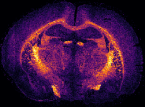

In MS imaging, data is collected from different positions in the sample, resulting in mass spectra as shown above. When the imaging analysis is complete, a single mass peak and its m/z value can be selected from the spectral data, representing a single compound detected in the sample. By plotting the intensity of this mass peak from each analysed position, MS images (heat maps) can be generated to show its relative change and thus how the compound is distributed in the sample area. For example, negative ion IR-LAAPPI MS images of a 20 μm thick slice of whole rat brain tissue measured at 70 μm spatial resolution, consisting of approximately 30,000 pixels, are shown below to illustrate how different lipid species are distributed in the brain.

| Photo | MS image | MS image | MS image |

|---|---|---|---|

![]() |

| Myelin-stained brain | GalCer(38:1) | PE(34:0) | PE-P(36:4) |

Conventional imaging techniques such as positron emission tomography, autoradiography, and immunohistochemistry, can only image a few radiotracers, radioisotopes, or antibody-labeled molecules at a time, respectively, as presented with the myelin-stained photo above. MS imaging techniques like IR-LAAPPI and IR-LAESI can image hundreds of compounds simultaneously, thereby providing a valuable tool for finding differences between sample types such as malignant and benign tumors.